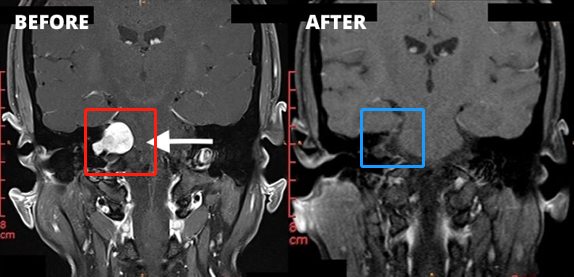

红色为患者术前核磁:右侧桥脑小脑角区见一类圆形占位性病变,边界清楚, T2WI高信号,其内信号欠均匀,增强扫描后病变呈明显强化,同侧桥脑小脑角池扩大,内听道扩大,四脑室轻微受压;

蓝色为患者术后核磁:术后肿瘤切除干净,巴特朗菲教授做到了全切全切,核磁未见占位性病变。

患者术后情况:张先生术后1周便出院,肿瘤全切、听力并未受损也没有面瘫。在术后9个月的随访中,张先生表示自己预后情况很好,已恢复正常生活,肿瘤也没有复发,感谢巴特朗菲教授。